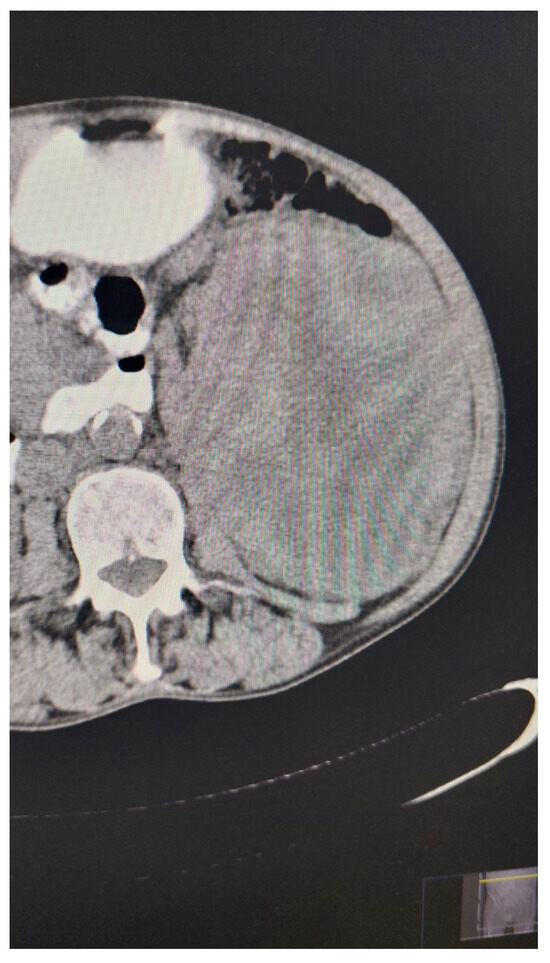

The previous experiments involved filtering images noised with different percentages of salt and pepper noise using the median filter (VMF) and the fuzzy filter (FF). Now, we apply other types of noise (Figure 4a–c), to the same original image Figure 1 using the appropriate functions in the MATLAB package.

The programs we use are coded in the MATLAB package, and to test image quality, we use the UIQI quality index (Z. Wang and A.C. Bovik [32]). For testing the sharpness of the filtered images, we use the metrics defined in the paper by N.D. Narvekar and L.J. Karam [33]. Note that the UIQI index and sharpness values range within the interval [ 0 , 1 ] , where values closer to 1 indicate better filtering quality and image sharpness.

In the algorithm for fuzzy filtering of images, we use a metric c defined as above in (15). The fuzzy metric used to measure similarity in brightness level among pixels is given in (16), with the parameter m = 2 . The tested values of the parameter K appearing in these metrics ranged from 0 to 5000, with a step of 500.

The fuzzy metric that considers the spatial distance between pixels is given in (17) and the tested values of the parameter t appearing in those metrics ranged from 0 to 5000 with a step of 500.

For the median filter, the obtained results are given in the Table 1:

For the fuzzy filter, the obtained results are given in the Table 2:

When considering the fuzzy metrics with parameter K = 500 , the image filtered by FF exhibits the best UIQI index.

We note that the median filter gives a higher UIQI quality index for images obtained by removing noise from the noised original images, for all types of noise considered (Table 1 and Table 2). The sharpness of the filtered images using FF is noticeably better than that of images filtered with VMF (Table 1 and Table 2).

If we look at the fuzzy metrics parameters that occur with FF, the best UIQI index is achieved with images where K = 500 .

Figure 4. (a) Contaminated image by Gaussian noise. (b) Contaminated image by Poisson noise. (c) Contaminated image by speckle noise.

Mathematics 12 02333 g004